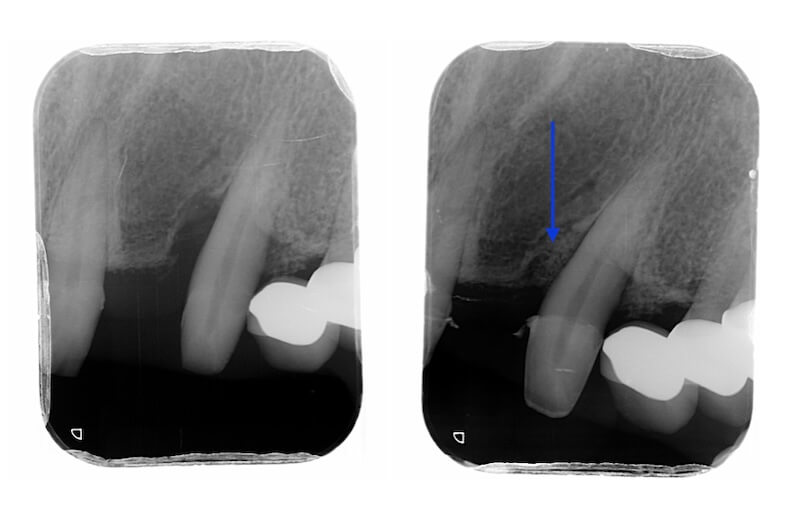

Ms.H 是屬於第一種並且血壓已控制良好的高血壓患者。因此我們會在拆除她的舊假牙之後再開始進行全口牙周治療。拆除假牙後發現右上的側門齒是齒質不足的殘留牙根,因此預計在之後治療牙周病時同時拔除該患齒。

拆除舊假牙:釐清殘留牙根與齒質狀況

拆除舊假牙換上臨時假牙之後,開始進入牙周病的療程。我們會先將治療前口內狀況完整記錄,詳細分析每一顆牙齒的牙周狀況。